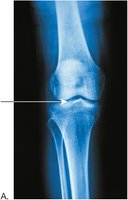

Osteoarthritis is a degenerative joint disease characterized by the breakdown of articular cartilage and narrowing of joint space.

Symptoms include pain, stiffness, and reduced mobility.